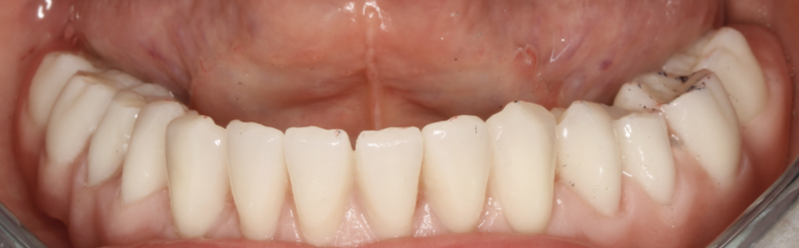

Mai întâi se realizează bara (Fig. 3.9.10) peste care se va aplica viitoarea lucrare. Apoi se realizează o machetă a lucrării pentru a analiza corectitudinea ocluziei (mușcăturii) (Fig. 3.9.11) precum și înălțimea dinților și aspectul facial al pacientului (Fig. 3.9.12, și Fig. 3.9.13).

Aspectul lucrării este unul natural, aceasta îmbunătățind estetica generală și fizionomia pacientului prin redarea conturului feței și plenitudinii obrajilor și a buzelor. Refacerea funcției masticatorii și redarea fizionomiei va aduce o îmbunătățire semnificativă a calității vieții pacienților care aleg acest tip de tratament (Fig. 3.9.15).